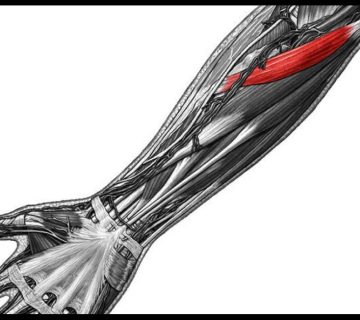

شاخه های شریان رادیال از سطوح لبه پشتی یک سوم دیستال و سطح خارجی کف دستی وارد اسکافوئید ( Scaphoid ) میشوند ( شکل ۴ ) . خونرسانی یک سوم پروکسیمال اسکفوئید از شریانهای بین استخوانی تامین میشود و مستعد ریسک برای نکروز استخوانی (مرگ بافت استخوانی درنتیجه فقدان خونرسانی) است.

(شکل ۴ ) : خونرسانی استخوان اسکافوئید.